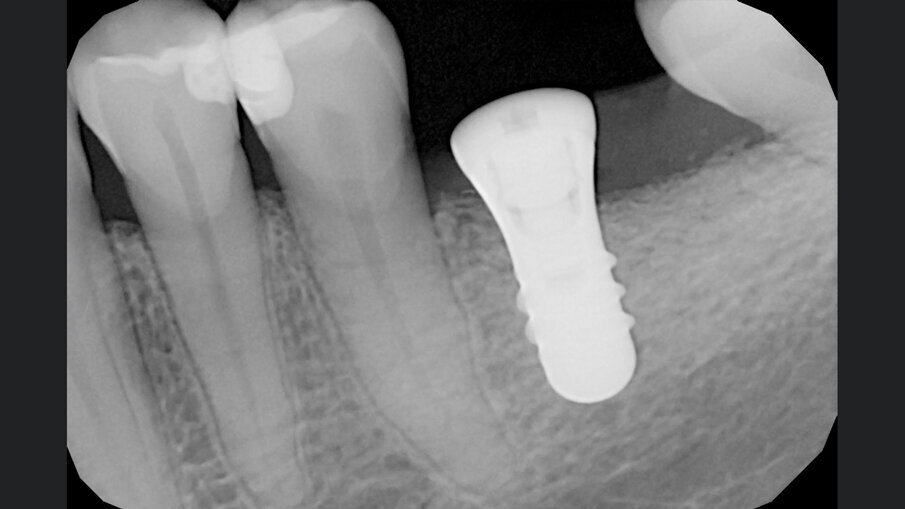

Gli innesti eterologhi utilizzati, ottenuti mediante un processo di deantigenazione enzimatica (Zymo-Teck, Bioteck) sono caratterizzati dalla presenza della componente minerale inalterata e del collagene osseo in conformazione nativa. Grazie a queste proprietà, l’innesto viene riconosciuto fisiologicamente da osteoclasti ed osteoblasti3 e viene rimodellato con osso del paziente in tempi fisiologici4, 5. Inoltre, la lamina corticale di origine equina, subisce un ulteriore trattamento di parziale demineralizzazione, che espone il collagene preservato e ne permette la caratteristica flessibilità che la rende facilmente adattabile alle diverse geometrie della cresta alveolare6, 7. Veniva quindi inserito un impianto (Straumann Tissue Level 4,5 x 8,5 mm), l’ISQ di 79 suggeriva la simultanea inserzione della vite di guarigione e tre mesi più tardi veniva consegnata la protesi definitiva in zirconia (Figg. 6-8). A 24 mesi dalla consegna della protesi, veniva eseguita una RX di controllo che mostrava un ottimo mantenimento volumetrico dell’osso alveolare (Fig. 9).

Fig. 7 - RX post-operatoria.